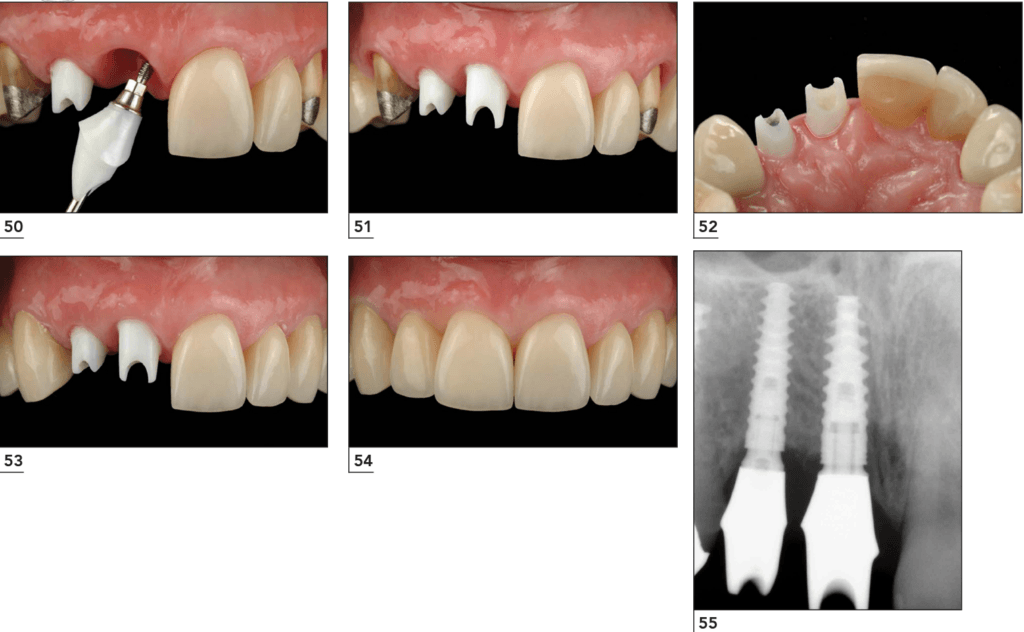

Clinically, the Digital Customized Technology customized implant placement is performed through the following 4 steps:

Step 1: Implant placement using a surgical guide.

Instead of using the freehand technique based on clinical experience, the personalized implant solution uses a surgical guide template to ensure the most accurate implant placement.

Step 2: Placement of customized healing abutment to shape periodontal tissue.

The customized healing abutment is usually placed immediately during implant placement. In some cases where there is insufficient bone or gingival volume, Healing Customized may be placed after 2 months, once the implant has integrated.

Step 3: Scanning periodontal tissue, occlusion, and implant position to fabricate customized abutment and crown.

Scanning is performed after the implant has integrated and stabilized, usually 2 months after implant placement.

Unlike traditional implant methods that use manual impressions, personalized implants use scanning technology for impression taking. This technology not only accurately records the implant position but also precisely captures the morphology and structure of periodontal tissues and the patient’s occlusion to transfer into virtual design software.

Step 4: Placement of the customized abutment and fixation of the ceramic crown.

After scanning, the data is sent to the design center for simulation. The customized abutment is manufactured there and then placed intraorally. The abutment is designed to fit precisely with the periodontal tissue structure.

Step 2: Implant placement.

Once the guide and healing abutment are manufactured, the patient will be scheduled for surgery. Thanks to the guide, implant placement with Digital Customized Technology is usually quick and gentle. This is the second appointment, typically about 3 days (36 hours) after the first appointment.

Step 3: Placement of the customized healing abutment.

The customized healing abutment may be placed immediately after implant placement (in most cases) or during a second stage once the implant is stable. If placed in the second stage, another appointment will be required, typically 2–4 months after implant placement depending on the implant type.

Most cases have the healing abutment placed during implant surgery, which is an advantage of the solution because it reduces the number of surgical procedures.

Step 4: Scanning the implant position, periodontal tissue, and occlusion.

After the implant has integrated and stabilized (2–4 months), the patient returns to the clinic where scanning technology is used to capture the entire oral structure.

Step 7: Placement of the customized abutment and ceramic crown.

OAfter manufacturing, the abutment and crown are returned to the clinic. The dentist schedules the patient for placement of the customized abutment and ceramic crown.

This is the fifth appointment and usually occurs about 5 days after the scanning appointment.